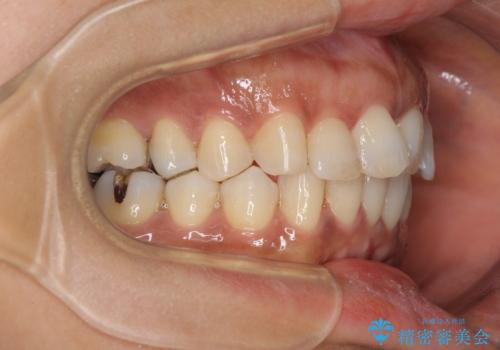

- 上下前歯のデコボコ改善をインビザラインにて行いたいとのことで来院された患者様です。

インビザラインをご希望のことで、IPR(歯と歯の間を削る)などによりスペースを獲得して、排列していくこととしました。

骨格的に上下顎が左右にずれていたため、正中位置は現状を維持したまま歯列不正を解消していくことになります。

なかなか装着時間が守れず、後戻りを繰り返しながら治療を進めたため、インビザライン治療期間期限ギリギリの5年弱の期間を要しました。